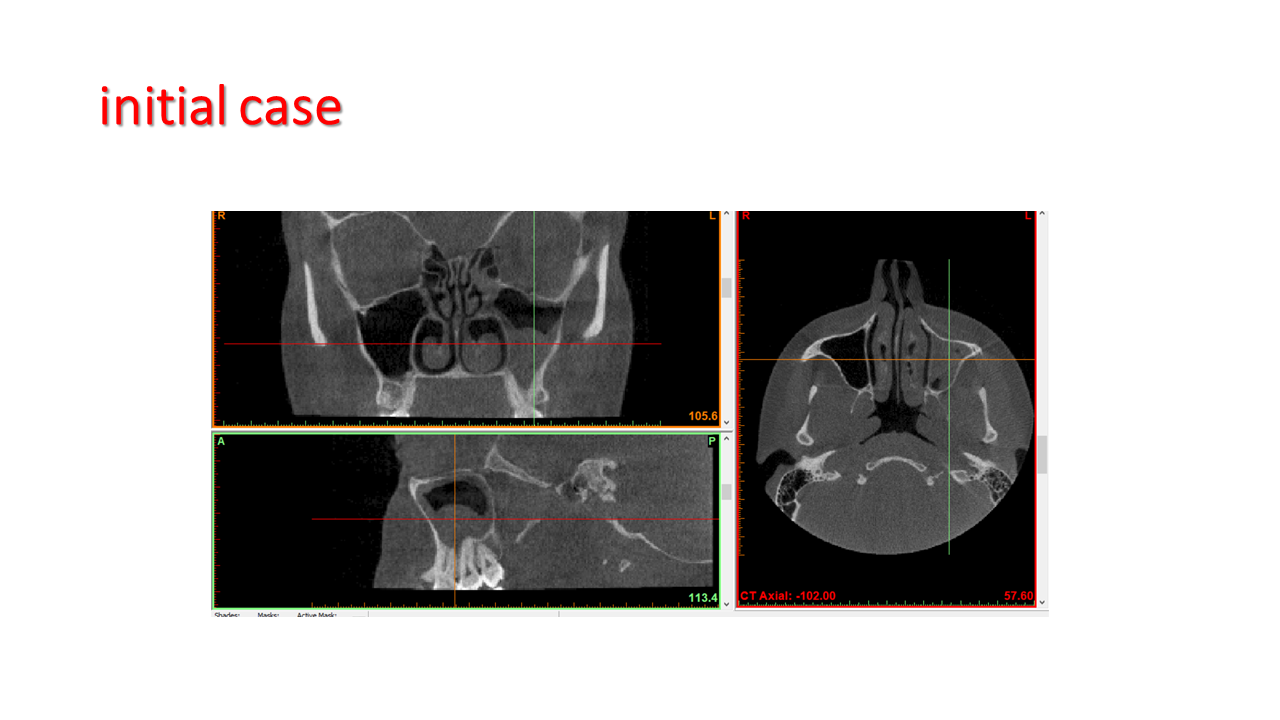

FESS Case Review and Radiologic Analysis (30.09.2016)

Case-based presentation focused on pre- and postoperative imaging in functional endoscopic sinus surgery (FESS). Includes anatomical landmarks, surgical variations, sinus pathology, and technique evaluation. Delivered by Dr. Levon Galstyan at AAOMFS.